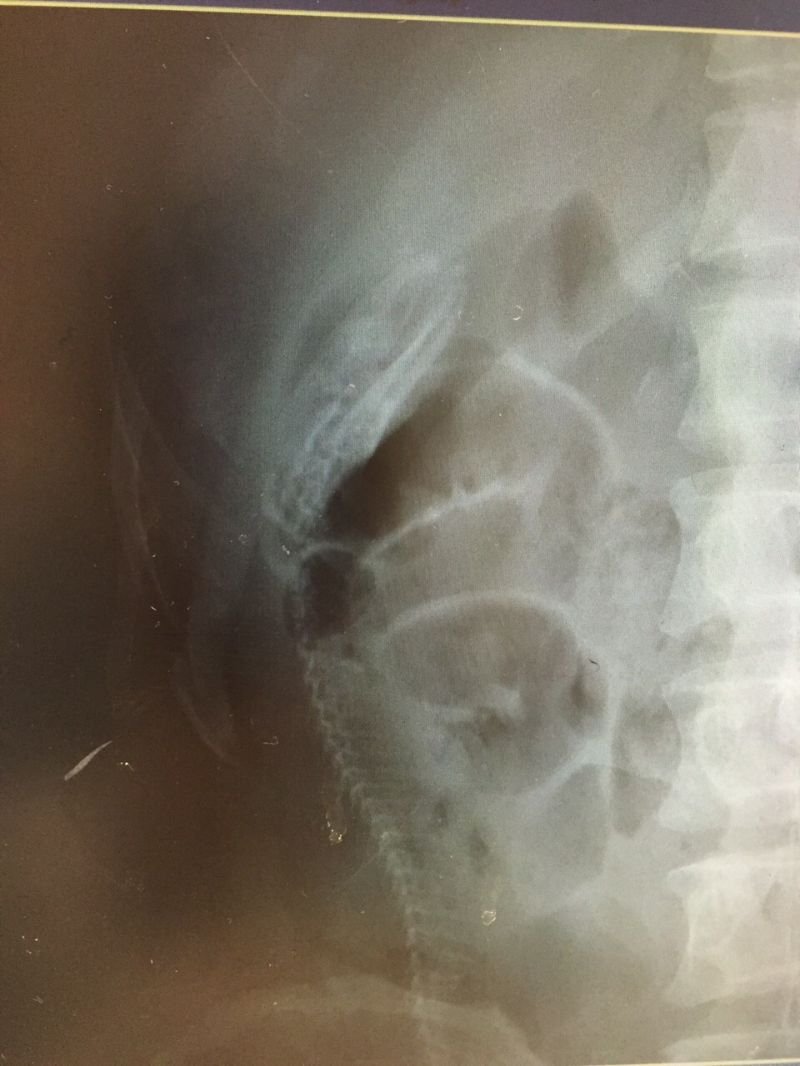

Разгляди на рентгеновском снимке позвоночник угря (18+)

Мужик обратился за помощью в больницу с жалобами на острую боль в кишечнике. Рассказал, что смазал угря лубрикантом и засунул себе в зад, чтобы получить удовольствие. Получил еще какое. Скользкий хвост выскочил из пальцев, и угорь "поплыл", прогрызая кишки на своем пути. В общем, дядьку внутри истерзал серьезно. Жесть.. фу... блуээээ :)